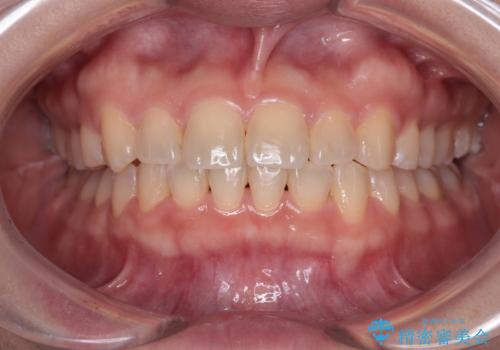

八重歯を治す 非抜歯のワイヤー矯正治療

舌の突出癖により上下前歯が開咬となりましたが、舌のトレーニングと顎間ゴムの使用により、元々の被蓋関係に改善することができました。

アンカースクリューを用いて、出っ歯仕上がりを回避し、正中位置も改善することができました。